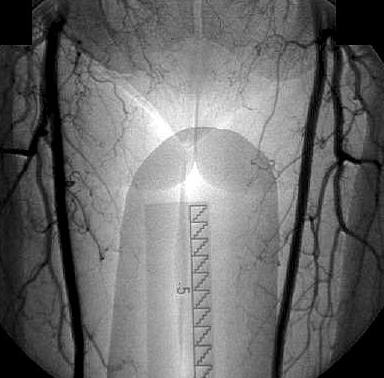

the pathological image-left and the physiological image-right

If you need

a physiological image to compare click here